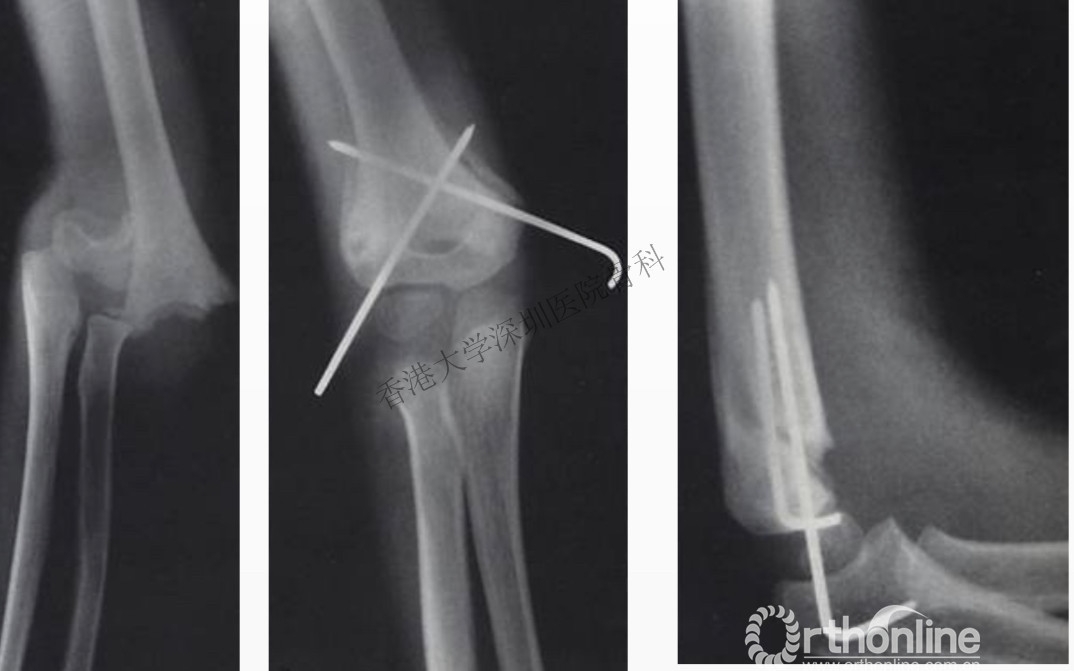

肱骨髁上骨折,经皮克氏针固定

手法复位后不稳定的II型及III型骨折需行经皮克氏针固定。外髁两枚克氏针或内外侧各一枚克氏针交叉克氏针固定均可,两针在骨折线平面相距越远则固定越稳固,应避免在骨折线平面交叉。